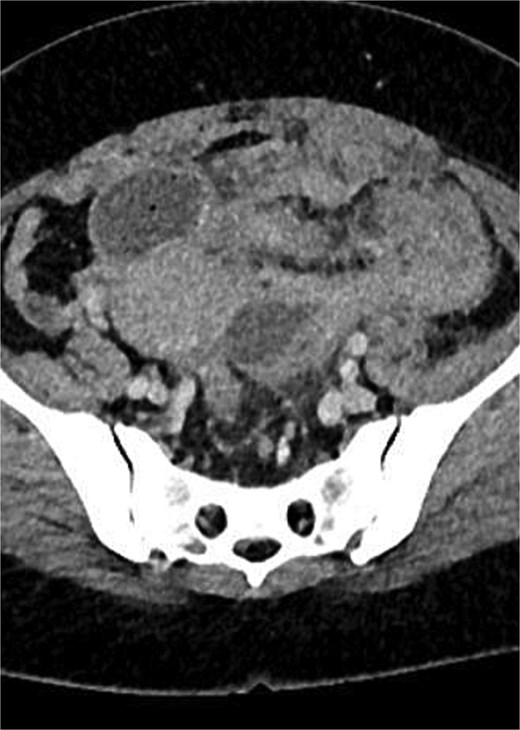

A computed tomography (CT) scan of the abdomen and pelvis showed complex and aggressive disease involving the pelvic area, affecting the urinary bladder, cervix, sigmoid colon, and the left adnexa. Additionally, a loop of small bowel was involved in the inflammatory process, leading to a closed-loop small bowel obstruction. Differential diagnoses included infiltrative malignancy, tuberculosis, or actinomycosis. A CT scan of the thorax was performed to rule out any pathology or metastasis to the lungs.

CT images with Fig. 1: Pelvic mass involving sigmoid colon, uterus, urinary bladder, left fallopian tube and ovary. Figure 2: Small bowel obstruction secondary to the mass.

CT scan of abdomen and pelvis: Pelvic mass involving sigmoid colon, uterus, urinary bladder, left fallopian tube and ovary.